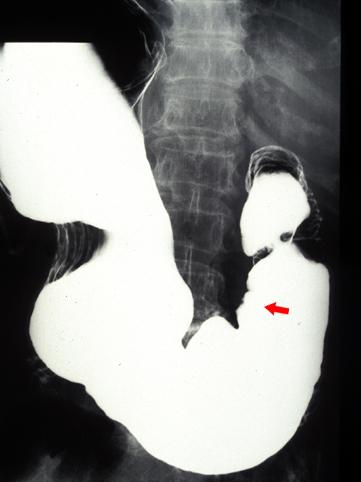

疾病(病理主体)的分类恶性上皮性肿瘤/腺癌

部位(按器官分)胃(部位)/前庭

检查方法X线

肿瘤的肉眼分类0型(表在型)/IIa型(IIa+IIc)

肿瘤最大直径20~24

肿瘤的深度sm